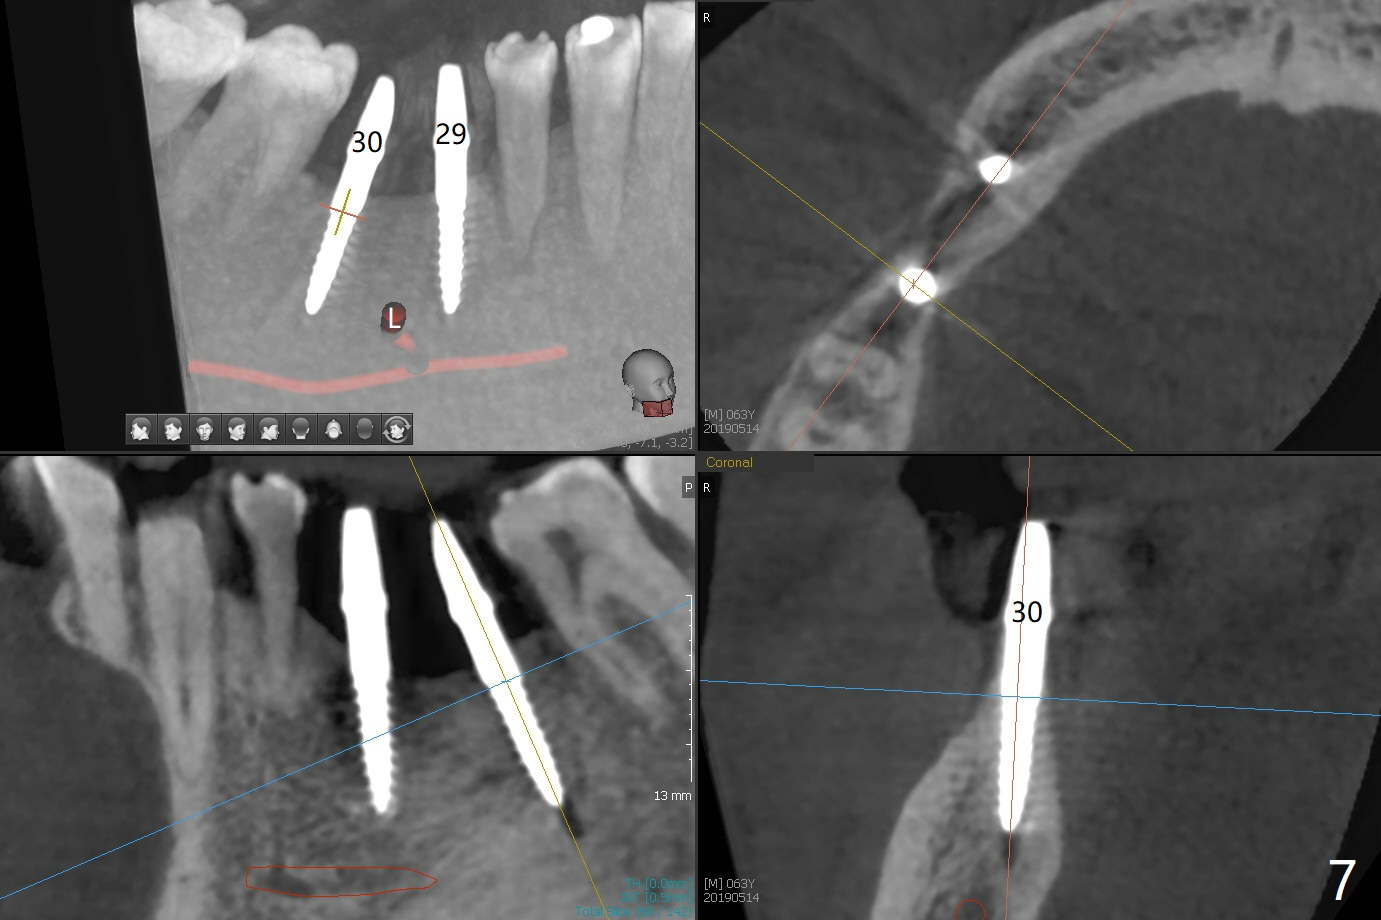

After initial osteotomy using 2.2 mm drill for 10 and 11.5 mm at #29 and 30, respectively, the guide is removed for re-insertion of drills and PA (Fig.1). The osteotomy at #29 is found lingually and in the nonkeratinized gingiva with mild laceration (wish incision to be made before osteotomy); the osteotomy is established a little lingual at #29 (Fig.2) and more or less in the middle of the narrow ridge and #30 (Fig.3). Lindamann bur is used to move #29 osteotomy buccally. A 1.5 mm drill is used to increase the depth free hand before placement of 2.5x10(4) mm 1-piece implants (Fig.4). After adjustment of the implant depth (Fig.5), CT is retaken, which shows proper implant placement (Fig.6,7). Probably due to good oral hygiene, the gingiva around the implants appears to be keratinized 4 months postop (Fig.8). After abutment preparation for margin and parallelism, impression is taken (Fig.9). When the permanent crowns are temporarily cemented, the large gingival embrasure is noted (Fig.10,11). The latter could be reduced by modifying the provisional in the healing stage. In fact the crown at #29 dislodges 2 days post cementation because lingual (Fig.12) and distal (Fig.13) placement. A surgical stent should have been fabricated from RPD for free hand placement!